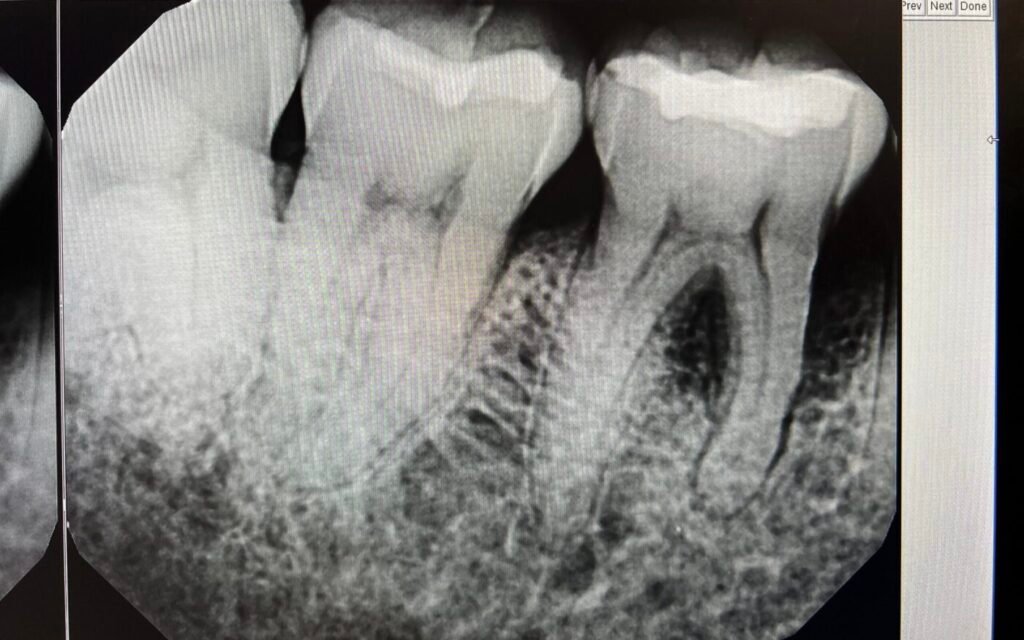

We perform a detailed exam, measuring gum pockets and using digital X-rays to assess bone density and the extent of the infection.